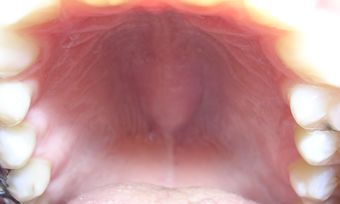

Palate exhibiting torus palatinus. | |

الحنك (بالإنجليزية: palate)هو التركيب الفاصل بين جوف الأنف وجوف الفم فهو سقف الفم وأرضية الأنف. يمتد الحنك نحو الخلف ليفصل جزئياً بين البلعوم الأنفي والبلعوم الفموي. للحنك شكل القبة وهو يتألف من قسمين هما الحنك الصلب الذي يشكل الجزء الأمامي والحنك الرخو الذي يشكل الجزء الخلفي منه.